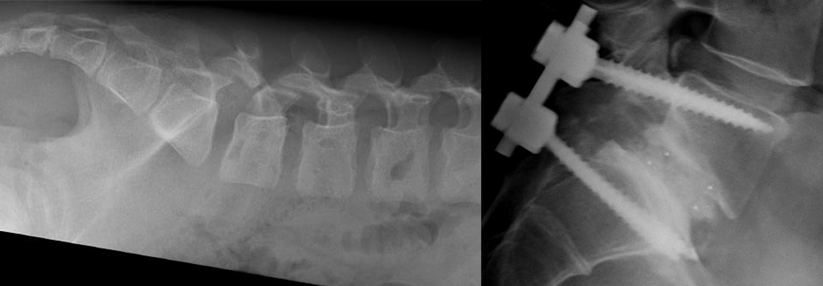

An den Querfortsätzen der LWS fixiert, stimulieren die Elektroden den Ramus dorsalis der Spinalnerven.

Einer der ersten Orthopäden, die das System hierzulande verwenden, ist Dr. Jan Schilling von der Abteilung für Wirbelsäulen- und Neurochirurgie am Krankenhaus Tabea in Hamburg. Infrage kommen Patienten mit chronischen unspezifischen Rückenschmerzen ohne Indikation zu OP oder spinal cord stimulation nach erfolgloser konservativer Therapie. Bei dem minimalinvasiven Eingriff platziert Dr. Schilling zwei Elektroden an den Querfortsätzen der LWS, die den Ramus dorsalis der Spinalnerven stimulieren. Über Koinnervation erreichen die Impulse die Tiefenmuskulatur der angrenzenden Wirbel. Die zugehörige Batterie mit Impulsgeber findet s.c. im Gesäß ihren Platz.